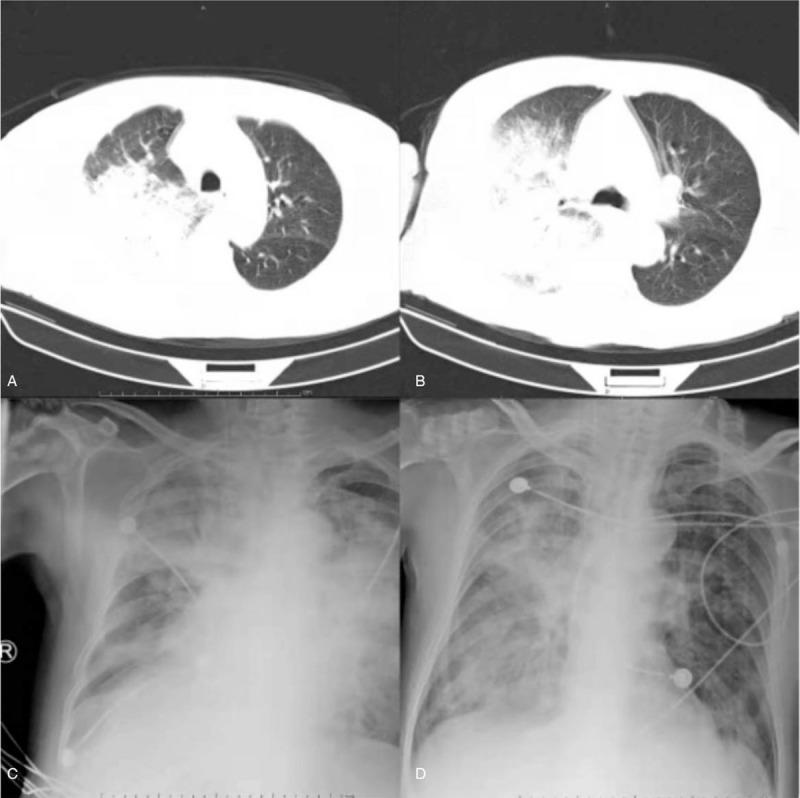

The patient's body temperature and infection indicators improved and the chest X-ray findings showed the amelioration of lesions after 18 days of treatment. The patient was discharged without treatment on hospital day 19 due to financial constraints and subsequently died after 7 days.

经过 18 天的治疗,患者的体温和感染指标得到改善,胸部 X 光检查显示病变改善。由于经济拮据,患者在住院第 19 天出院,随后在 7 天后死亡。